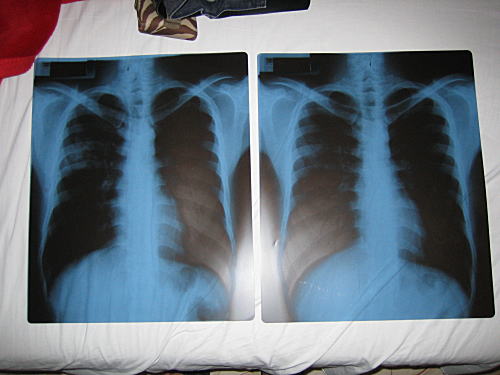

↓肺炎療養中の人のレントゲン。イヤよ、そんなところまで見ないで……。

しかし気を抜いてはいけない。なんでもSARS以来中国での入国管理は非常に厳しくなっているらしく、センサーで入国者の体温を計りわずかでも熱があると入国を拒否されるそうだ。荷物検査も当然のようにあるのだが、そんな状況でもし入国者(オレ)の荷物から

肺炎の症状がよく表れているレントゲンが出てきたらどうなるか。おそらく、1万%の確率で入国禁止を言い渡されるはずだ。仮に「あれ? 肺炎のレントゲンって持ち込み禁止だったんですか?? わかりました。じゃあいったん預けます。また向こうで返して下されば結構ですから」とトボけて自分だけ入場しようとしても、中国の役人に冗談は通じずタコ殴りにされると思われる。

そもそも危険なのはレントゲン写真自体ではなくオレの方なのだ。仮にオレかレントゲンかどちらかに入国許可が出るとしたら、

レントゲンの方である。レントゲン写真だけがオレを置いて入国し、そのままペラペラとめくれながら旅を続けるという状況にもなりかねない。

ということで、エノモト先生ごめんなさい!!

あの胸部レントゲン写真は、宿に置いて来てしまいました……。だって、旅を続けたいのはオレなのだからっ!! レントゲンがひとりで中国を旅したって、どうせ人見知りして現地の人になんて馴染めないに決まっているんだから!!